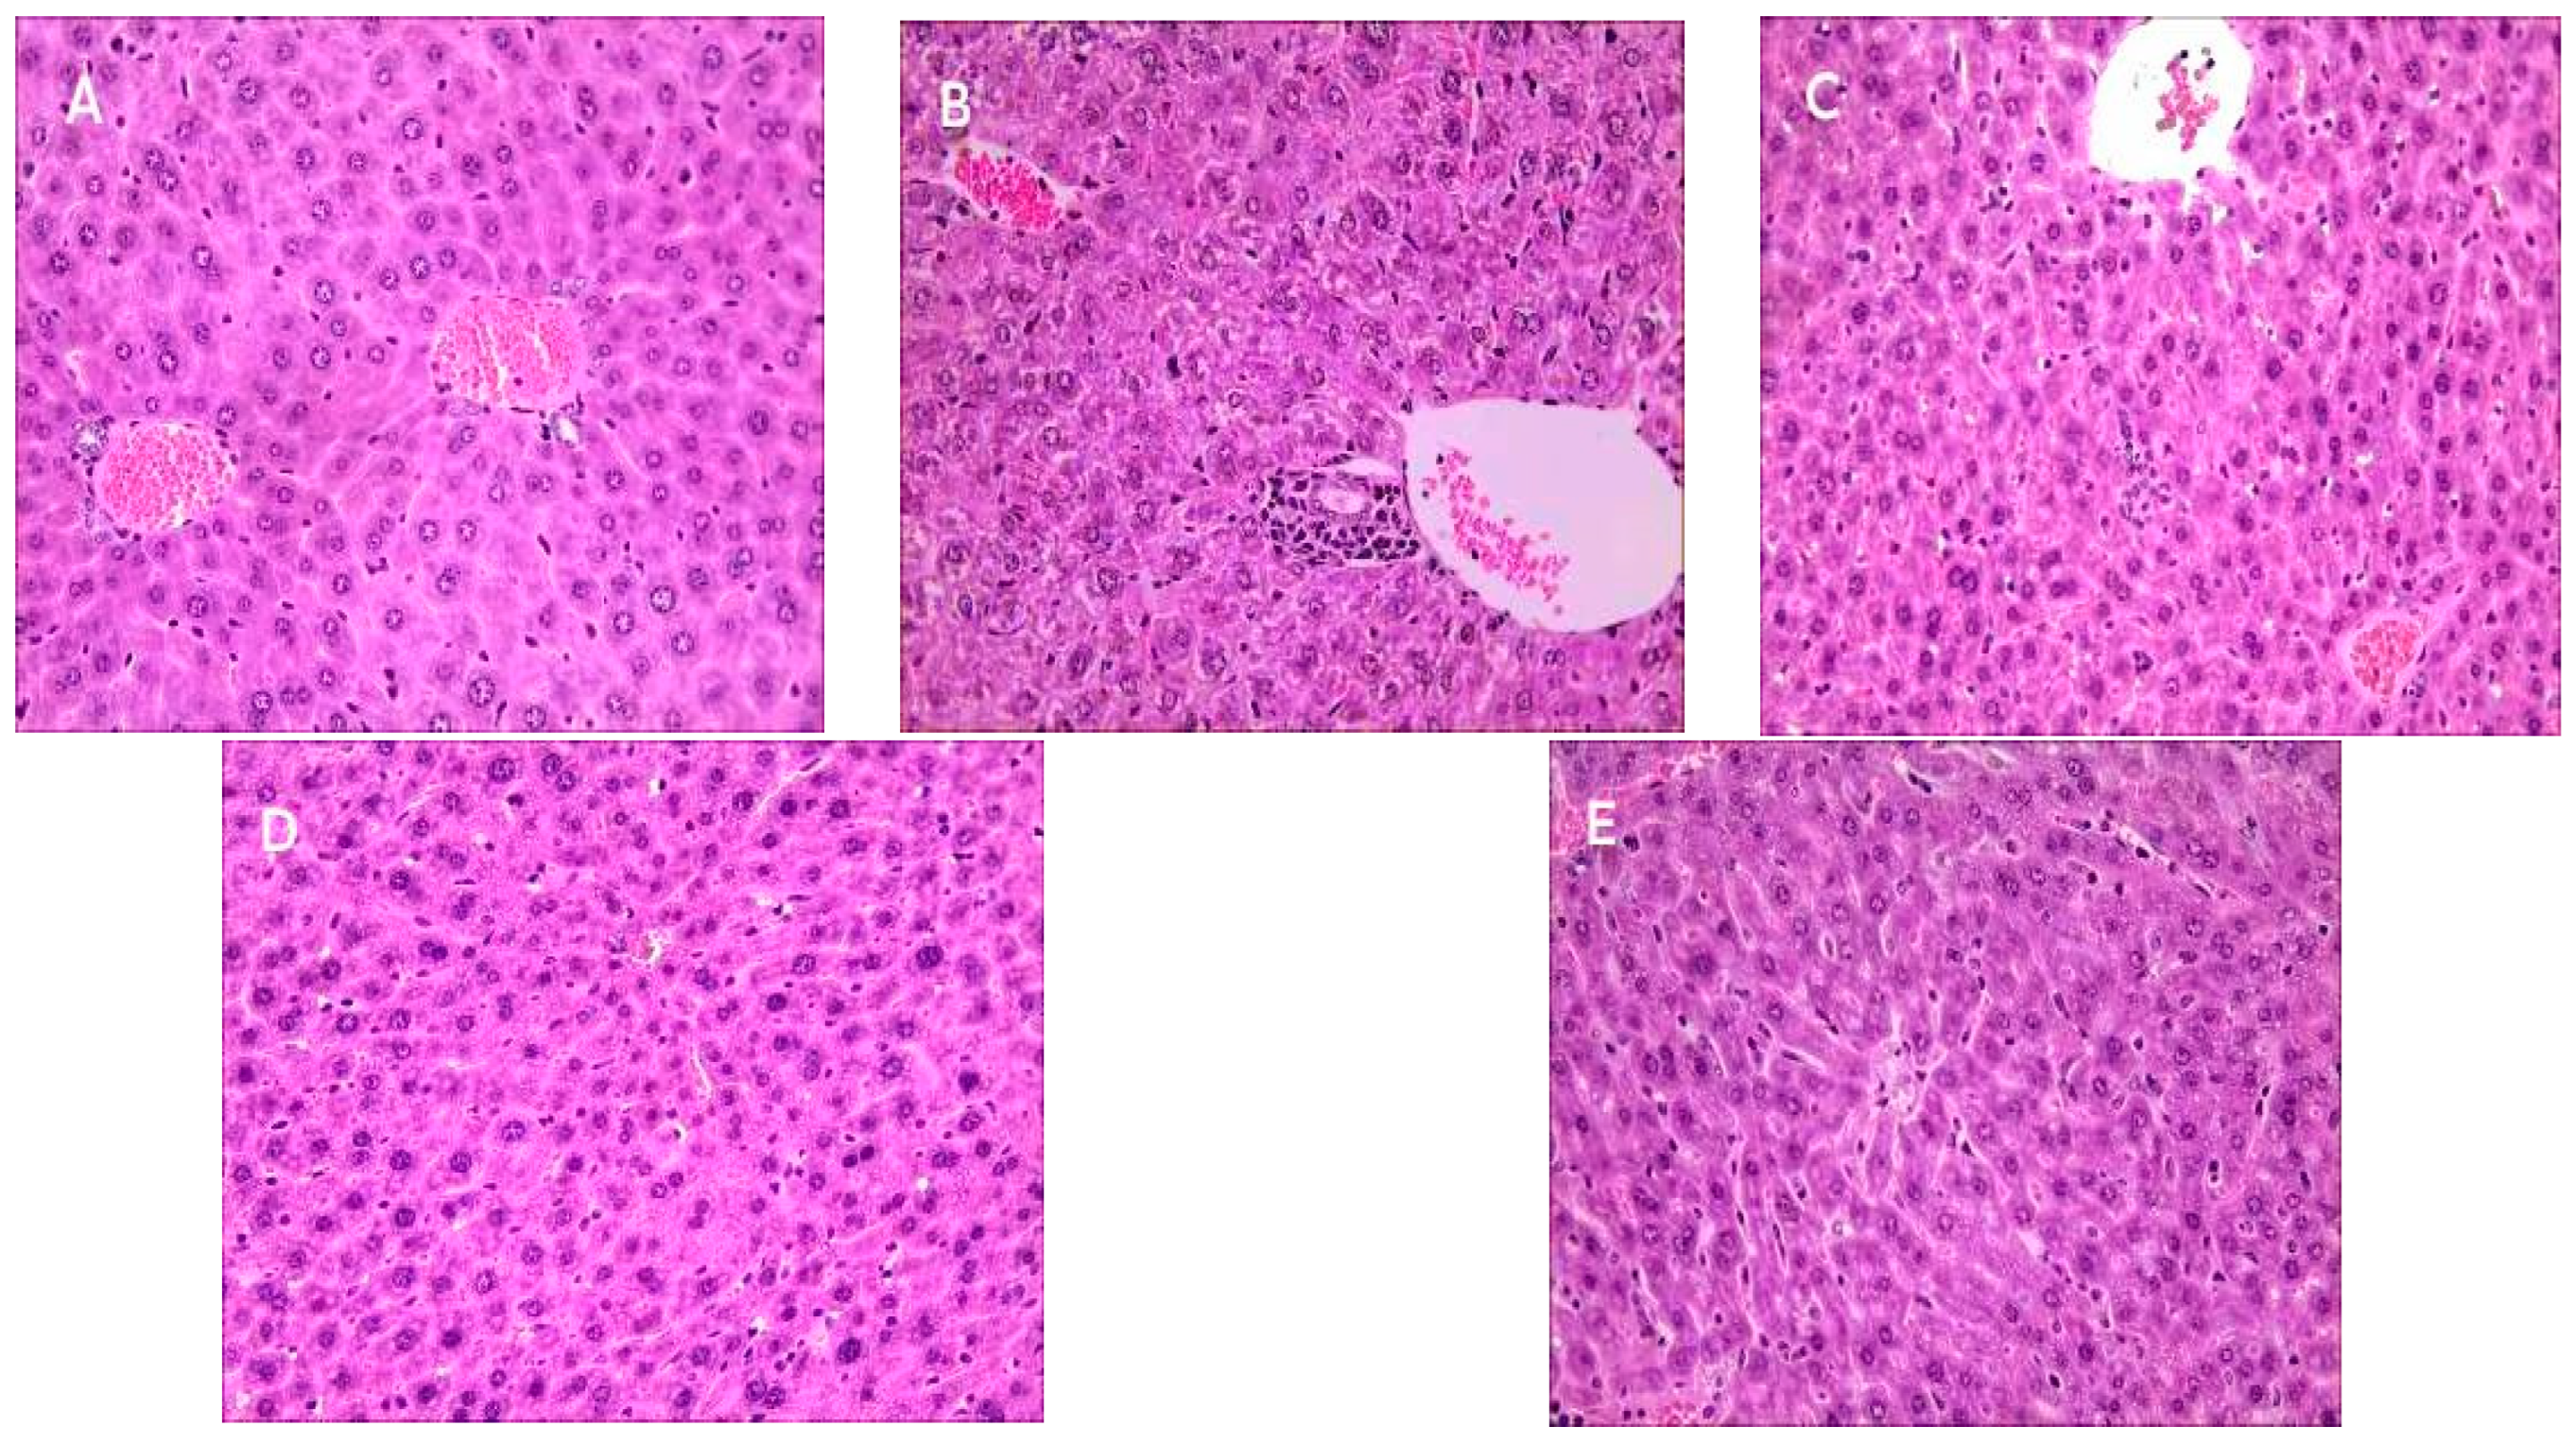

2.9. Effect of Se-OCAPIIA on the Morphology of Liver Tissue

3.12. Histopathological Analysis of Liver Tissues